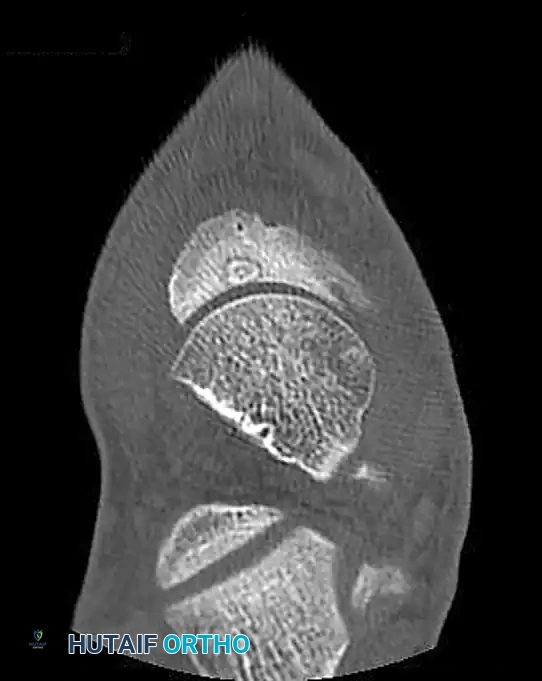

Determining the exact type and location of the tarsal coalition is critical for preoperative planning. Computed Tomography (CT) is the gold standard imaging modality for this purpose, providing high-resolution multiplanar views of the complex hindfoot articulations.

FIGURE 89-31: CT scan demonstrating a medial facet tarsal coalition of the calcaneus and talus in a young patient presenting with frequent ankle sprains.